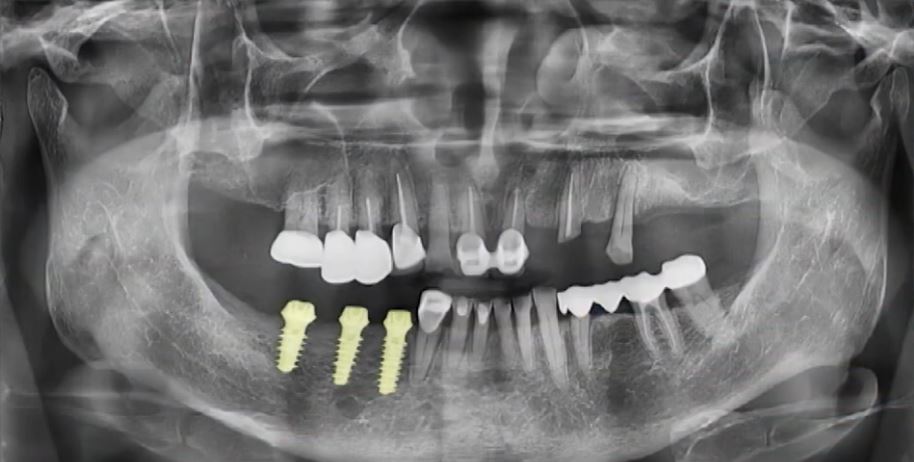

내비게이션 드릴을 이용해 진단핀을 제거한 후

임플란트를 식립한 최종 엑스레이 사진인데요.

매우 정확한 위치와 방향으로 식립된 것이 보이시죠?

정 중앙에 아주 정확하게

임플란트가 위치되어 있으며

심지어는 좁았던 잇몸뼈의 폭이

넓어진 것도 확인할 수 있습니다.